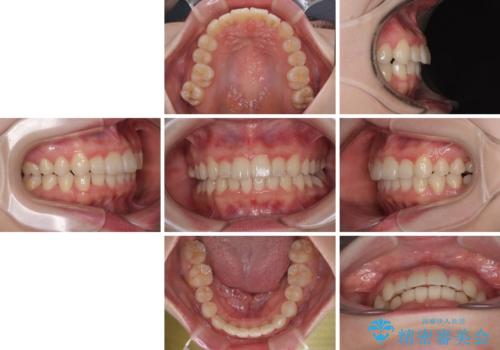

右上と左下の第一大臼歯2本が周辺の歯と比べて位置がずれていたため、ゴムかけやワイヤーに曲げを入れることで移動を試みましたが、どうよら癒着をしており、移動困難と判断されました。

見た目や咬み合わせに違和感がないとのことで、癒着歯の無理な移動は試みずに治療を終えることとしました。